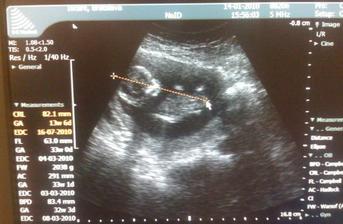

♥ Všetko v poriadku, srdiečko bije, máme 1,6 cm a termín pôrodu sa posunul na 17.7. 🙂

Tak co cert nechcel 17.12. sme boli u lekara troska skorej,zacali sme krvacat... ten strach nezelam nikomu na svete, bol neskutocny. Verdikt:mocove cesty. Vdaka Boze. Mame cca 2,6 cm a uz sa hybeme... 🙂

♥ 2.1. sme boli na kontrolnom ultrazvuku, máme 12,5 cm a prekrížené nožičky... 🙂 Sme v poriadku a veľmi sa z toho tešíme... 🙂